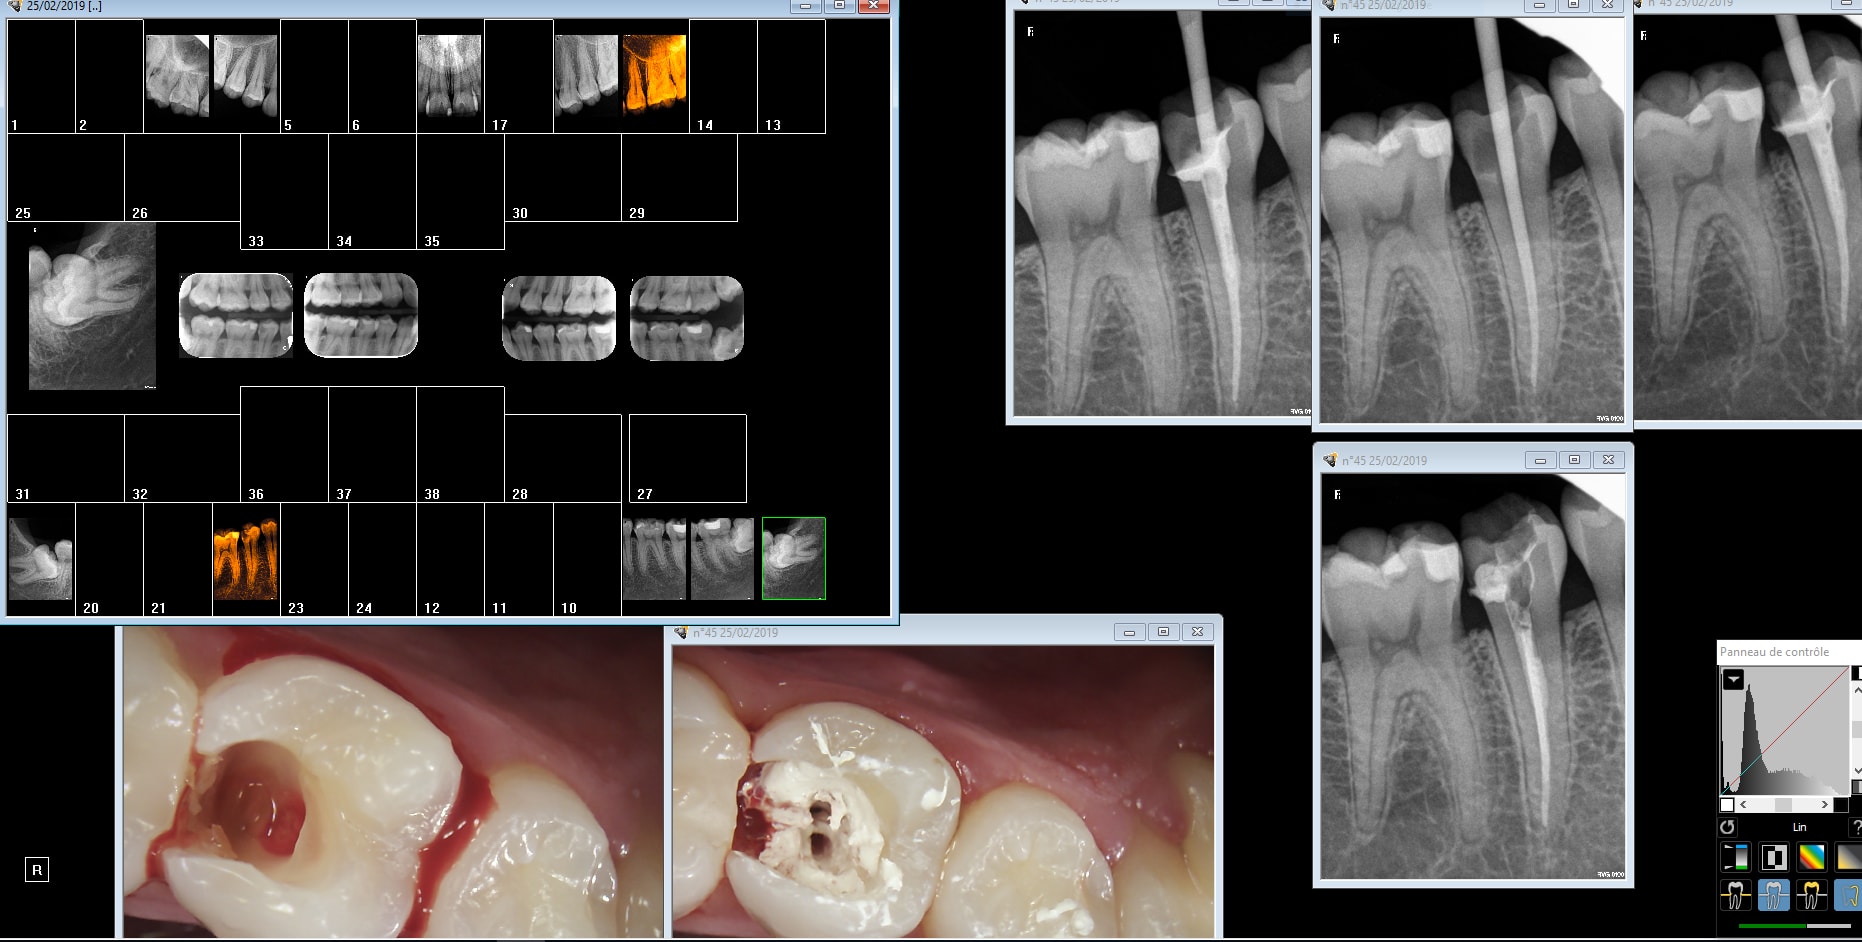

Comment placez vous votre cône pour bien voir les apex des 6 et 7 du bas sans faire mal au plancher de la bouche avec le capteur?

comme on me l'a appris à la FAC

Tube sous le rebord mandibulaire avec une orientation légèrement montante.

Incliner sous la branche horizontale le tube aussi ça marche...

Expliquer au patient que lorsqu'il ferme ça détend le plancher et ça fait moins mal. Lui dire de fermer dou ce ment

Ne pas utiliser de capteur trop epais qui passe pas....

Une des raisons pour laquelle j'utilise des plaques+angulateurs

meuler les angles du capteur ...

Ah oui mais sans la digue comme sur ta 45, c'est plus facile mon chicot !!! ;-)